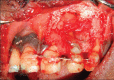

Palatogingival groove is an anatomical malformation that often causes severe periodontal defects. Treatments of such an anomaly present a clinical challenge to the operator. Careful endodontic and periodontal procedures may restore the form and function. In the present case; root canal therapy, apicectomy, and sealing of the groove with Biodentine™ were done. Bone graft was placed followed by platelet-rich fibrin (PRF) membrane. This treatment modality resulted in gain in attachment, reduction in pocket depth, and deposition of bone in the osseous defect. A 24 month follow-up is included.